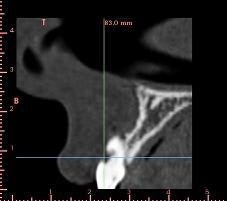

encore un ptit cas...sympa si on veut...car là j'ai besoin de l'expérience de ceux qui font çà souvent...

patient 17 ans...bientôt 18...

trauma dans l'enfance sur 11 et 21

pour la 21, çà va...mais la 11 est à bout de souffle...avec l'apex qui traverse la gencive vestibulaire...

veut un implant...forcément...mais là, faut une greffe...plutôt importante...

bon, autre truc plutôt défavorable au greffon ramique...je viens de vérifier: contact des apex de 38 et 48 avec le NDI...et comme les dds ont suffisamment de place...on laisse tranquillement évoluer...

sincèrement...j'ai pas trop envie de me casser la tête...

un greffon type puros ou biobank en bloc me semble être un bon compromis....

juste des particules d'os de synthèse...quid de la stabilité réelle du volume par rapport au bloc?

je sais que 17 ans c'est jeune...mais entre la greffe (bien 6 mois de cicat) la pose de l'implant (avec 3 ou 4 mois d'ostéointégration) on va vite être à 18 voir 19 ans...et là, je pense qu'on peut concevoir un ttm implantaire...non?